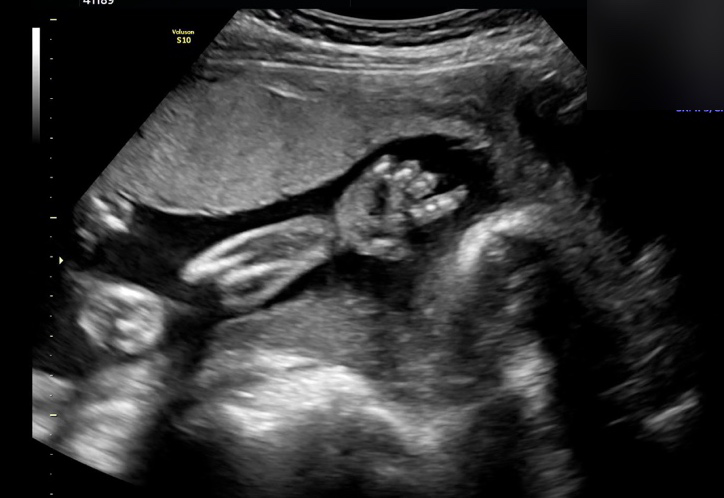

의무적으로 병원에 가 초음파로 아기가 잘 자라는지 보았다. 첫 번째로는, 병원에서 내원해야 하는 날짜를 정해줘서였고 두 번째로는, 정기검진일엔 회사를 쉴 수 있어서였다.

점점 신기해졌다. '꼬물이'란 말이 너무 잘 어울리는 모양새였다. 꼬물이가 커질수록 뱃속 생명에 대한 애착이 점차 커졌다. MBTI가 Power 'J'인 나는 일찍부터 인터넷 여기저기를 뒤져 아기 용품 리스트를 짰다. 하나둘씩 사는 재미가 쏠쏠했다. 아기용품을 구입하기 위해 애지중지 모으던 적금도 해지했다. 남편과의 대화는 온통 뱃속 아기로만 이루어졌다. 그래도 속상하지 않았다. 그렇게 많이 기다렸다.

34주 정기검진일, 산부인과에 방문하고 의사를 마주했다. 임신중독증이 심해 당장 전원을 하라고 했다. 오늘 출산해야 하냐고 묻는 친정엄마의 말에 그럴 수도 있다고 했다. 사실 새벽 내내 인터넷 서칭한 결과 내가 겪는 증상들이 임신중독증을 가리키고 있었기에 진즉에 나는 전원 할 병원도 알아봐 놓은 상태였다. 그렇게 다음날 전원을 했고, 전원한 병원에서는 아기가 이렇게 작은데 왜 몰랐냐는 말과 함께, 당장 입원해야 한다고 했다. 뇌 혈관이 지금 터져도 이상하지 않다는 것이었다. 예상했던 일이었지만 막상 들으니 무섭고 당황스러웠다.